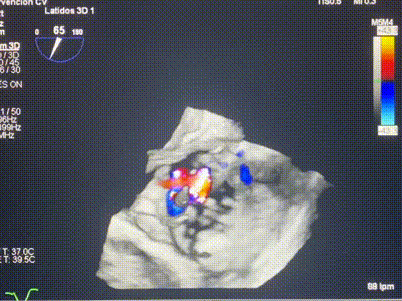

術(shù)前超聲提示重度三尖瓣反流

接受本次LuX-Valve Plus治療的是一位三尖瓣重度反流的高齡女性,患者早前曾由于二尖瓣疾病行經(jīng)導(dǎo)管二尖瓣置換術(shù),植入Tendyne瓣膜一枚,且有ICD植入史。術(shù)前CT分析結(jié)果顯示,瓣環(huán)大小為47.6mm,血管無(wú)明顯迂曲和鈣化。由于患者三尖瓣解剖結(jié)構(gòu)復(fù)雜,二尖瓣位人工瓣膜造成的超聲偽影和ICD導(dǎo)線的干擾使得歐洲沒(méi)有其他合適的商業(yè)化和臨床試驗(yàn)的產(chǎn)品可以對(duì)其進(jìn)行治療。經(jīng)過(guò)Rodrigo Estévez-Loureiro教授團(tuán)隊(duì)的詳盡術(shù)前評(píng)估,認(rèn)為L(zhǎng)uX-Valve Plus經(jīng)導(dǎo)管三尖瓣置換系統(tǒng)可以對(duì)該患者進(jìn)行有效的治療。因此,Rodrigo Estévez-Loureiro教授團(tuán)隊(duì)最終決定使用這一中國(guó)創(chuàng)新器械為患者進(jìn)行手術(shù)。法國(guó)波爾多里爾大學(xué)附屬醫(yī)院的Thomas Modine教授與加拿大圣保羅醫(yī)院的Anson Cheung教授全程線下指導(dǎo)本次手術(shù)。